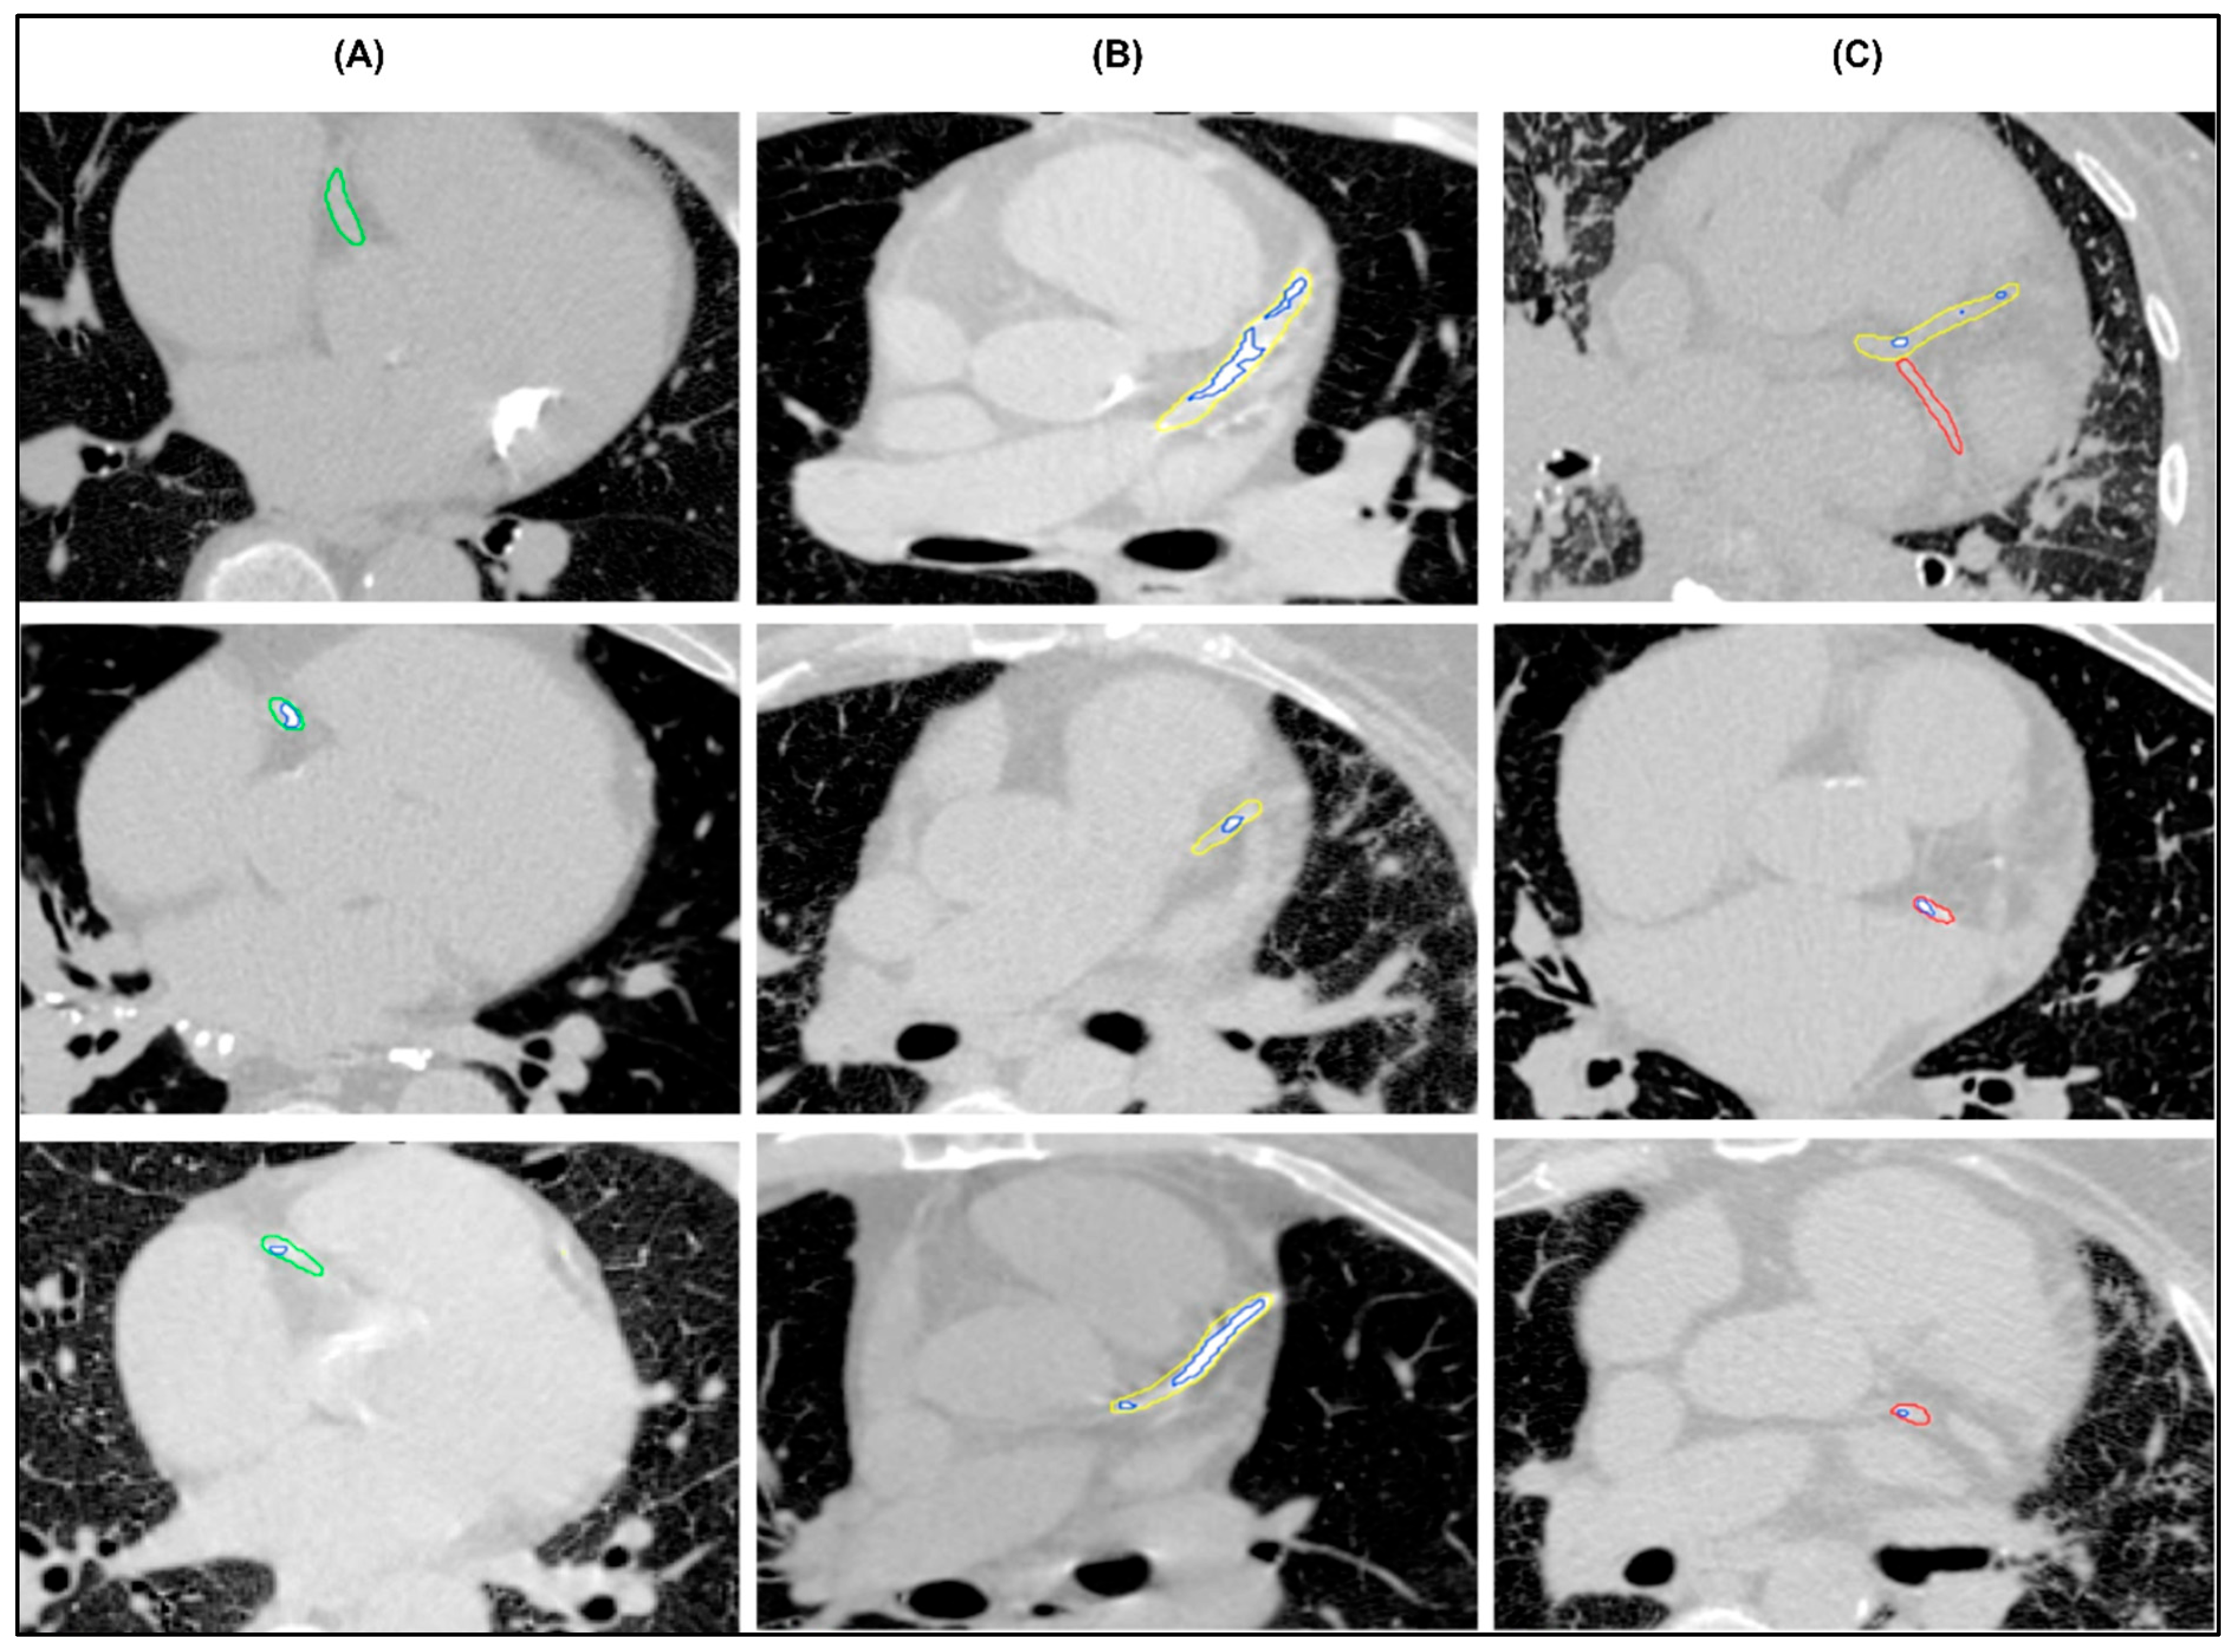

The proposed model was able to segment the coronary arteries and calcifications among the patients (Figure 3). Inter-observer agreement for the evaluation of AI-derived segmentations was assessed using free-marginal κ analysis, which measures the agreement between two raters, with values closer to 1 indicating stronger agreement. Visual assessment demonstrated high correlation among the two raters, with the majority of segmentations classified as excellent in both assessments (78.5%). Moderate to strong agreement was found for coronary artery segmentation, with κ values of 0.81 (95% CI 0.72–0.90) in the LAD, 0.76 (95% CI 0.66–0.86) in the RCA, and 0.68 (95% CI 0.57–0.79) in the LCX. Moderate to strong agreement was also found for calcification segmentation with κ values of 0.85 (95% CI 0.77–0.94) in the LAD, 0.85 (95% CI 0.77–0.94) in the RCA and 0.79 (95% CI 0.69–0.88) in the LCX. The full assessment results are summarised in Table 2.

Figure 3.

Examples of successful segmentations of (A) right coronary artery (green), (B) mainstem and left anterior descending artery (yellow), (C) left circumflex coronary artery (red) with multiple calcifications (blue).